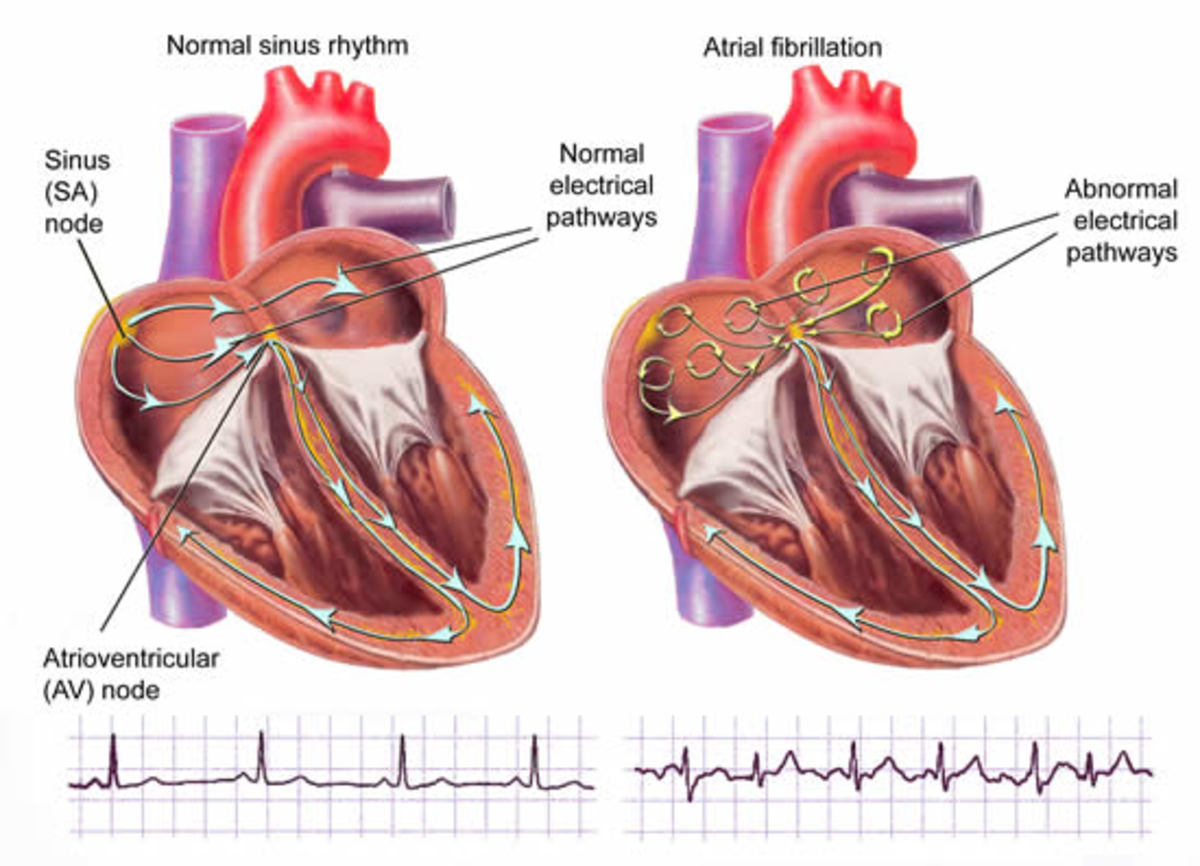

Στην κολπική μαρμαρυγή, ο καρδιακός ρυθμός μπορεί να φτάσει ακόμα και πάνω από 140 παλμούς το λεπτό. Η κύρια διαφορά μεταξύ ενός κανονικού ρυθμού και της κολπικής μαρμαρυγής είναι ότι δεν μπορείτε να προβλέψετε πότε θα είναι ο επόμενος καρδιακός παλμός. Αυτό συμβαίνει, επειδή υπάρχει ταυτόχρονα και αρρυθμία. Δηλαδή, κατά τη διάρκεια της κολπικής μαρμαρυγής, οι δύο άνω κοιλίες της καρδιάς χτυπούν ακανόνιστα και εκτός συγχρονισμού με τις δύο κάτω κοιλίες.

Ο φυσιολογικός καρδιακός ρυθμός ενός ατόμου θα πρέπει να είναι μεταξύ 60 και 100 παλμών το λεπτό όταν είναι σε κατάσταση ηρεμίας. Μπορείτε να μετρήσετε τον καρδιακό σας ρυθμό ψηλαφίζοντας τον καρπό ή το λαιμό σας.